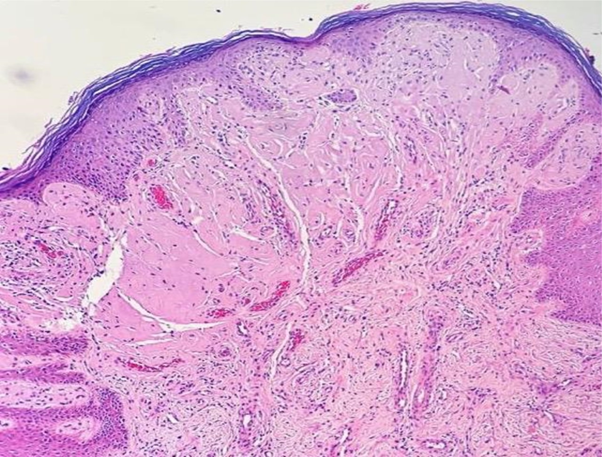

Porphyria was our main hypothesis, although porphyrins urine test was negative and no fluorescence was detected on the urine. Subsequently, a skin biopsy was performed, which revealed hyaline deposits in the papillary dermis and around the vessels that became more evident on Periodic Acid-Schiff (PAS) stain with diastase (Figure 3 & Figure 4). Immunohistochemistry was also performed, and revealed positivity for type IV collagen (Figure 5).

Figure 3 Histological skin sections show deposits of hyaline material in the papillary dermis and around vessels (hematoxylin & eosin).